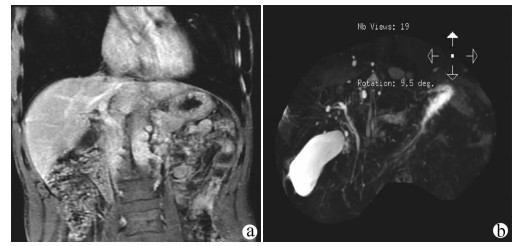

Hepatic alveolar echinococcosis misdiagnosed as intrahepatic cholangiocarcinoma: A case report

Kai ZHAO, Zhixin WANG, Shengbao WEN, Haijiu WANG, Haining FAN, Li REN

2021, 37(5): 1183-1185. DOI: 10.3969/j.issn.1001-5256.2021.05.042

Abstract(1037) HTML (359) PDF (2157KB)(63)

Abstract: